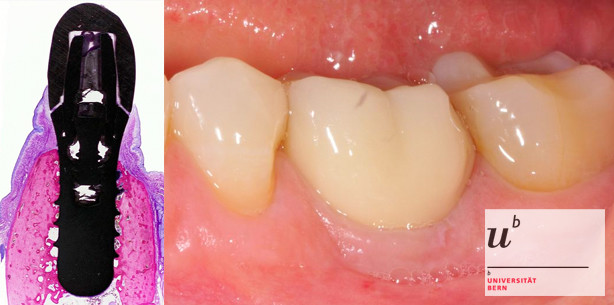

Foto: Foto: Uni Bern

Forschende der Zahnmedizinischen Kliniken (ZMK) Bern konnten in einer umfangreichen Langzeitstudie aufzeigen, dass bei der Routinebehandlung von Zahnimplantaten kaum Komplikationen auftreten und das Risiko für die Patienten somit gering ist.

Die Studie mit einer Laufzeit von zehn Jahren umfasste mehr als 300 teil-bezahnte Patientinnen und Patienten, bei denen Ende der 90er Jahre einzelne oder mehrere Zähne durch insgesamt 511 Implantate ersetzt worden waren. Dabei wurden Titanimplantate mit einer damals neuen mikrorauen Oberfläche verwendet, die noch heute eingesetzt werden. Die Nachkontrolle dieser Patienten ergab, dass über diese Zeit lediglich sechs Implantate nicht gehalten hatten, was einer Verlustrate von 1.2 Prozent entspricht. Weitere 1.8 Prozent der Implantate zeigten während dieses Zeitraums eine biologische Komplikation in Form einer Infektion.

Daniel Buser, Simone F. M. Janner, Julia-Gabriela Wittneben, Urs Brägger, Christoph A. Ramseier, Giovanni E. Salvi: 10-Year Survival and Success Rates of 511 Titanium Implants with a Sandblasted and Acid-Etched Surface: A Retrospective Study in 303 Partially Edentulous Patients, Clinical Implant Dentistry and Related Research, Dezember 2012, DOI: 10.1111/j.1708-8208.2012.00456.x